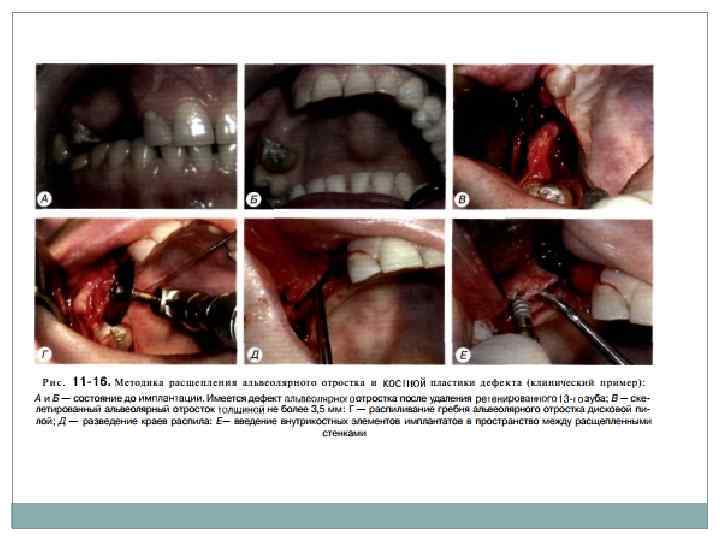

Расщепление альвеолярного гребня Первичная стабилизация имплантата зачастую невозможна в случае узкого альвеолярного гребня. Устранить горизонтальный дефицит костной ткани альвеолярного отростка верхней челюсти и альвеолярной части нижней челюсти можно за счет расщепления или расширения кости, и, таким образом, достичь достаточной ширины для препарирования имплантационного ложа. Суть метода заключается в продольной остеотомии альвеолярного гребня в саггитальной плоскости с помощью специальных инструментов, которые устанавливают между двумя кортикальными пластинами и которыми постепенно расширяют альвеолярную часть челюсти, перемещая вестибулярно щечную кортикальную пластину с частью губчатого вещества, что, в свою очередь, позволяет одномоментно или спустя 4 6 мес установить дентальные имплантаты стандартного диаметра. Вестибулярная кортикальная пластина надламывается по типу «зеленой ветки» , а образовавшееся пространство между кортикальными пластинами заполняется аллогенными, аллопластическими или аутогенными костными материалами.

Ширина альвеолярного гребня должна б ыть не менее 3 мм, в том числе содержать н е менее 1 мм губчатого слоя